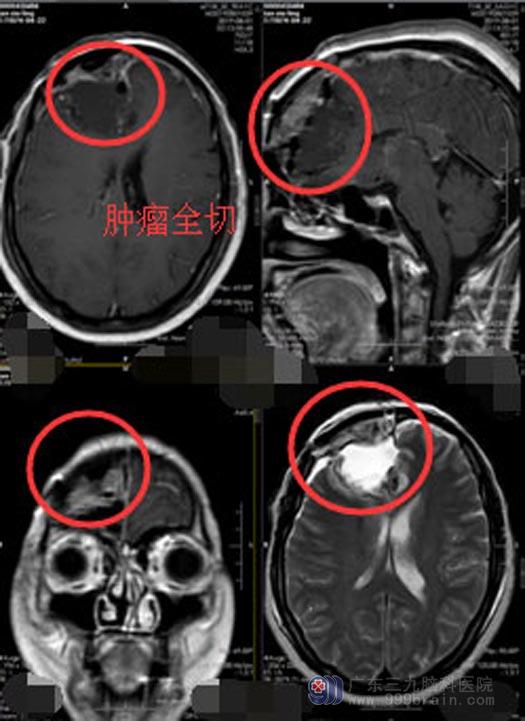

肿瘤位于功能区,家属同意择期行“麻醉唤醒下行右侧胶质瘤切除术”。医生在开颅手术过程中利用神经电生理技术精准定位,把病人唤醒,边交流边切除脑部肿瘤,病人根据医生指令配合手术,精准定位区分脑胶质瘤和功能区,在不误害脑功能区的前提下,将肿瘤全部切除,手术过程顺利。现谭阿姨已康复出院。

▲手术后